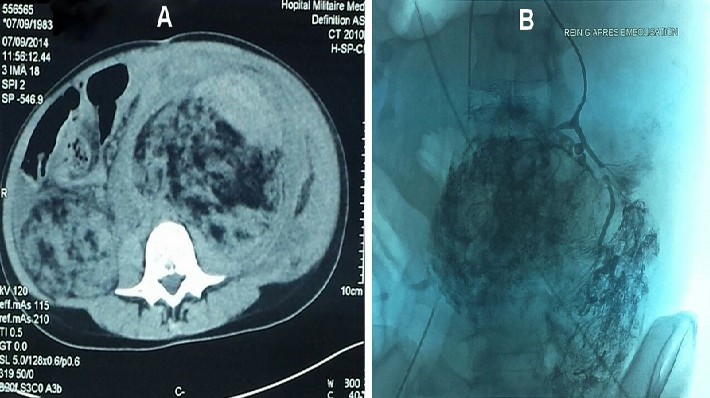

La sclérose tubéreuse de Bourneville (STB) est une phacomatose autosomique dominante en rapport avec la mutation de deux gènes suppresseurs de tumeurs TSC1 et TSC2. L'atteinte cutanée et neurologique est constante, celle des reins ou de la rétine est fréquente. Une patiente âgée de 28 ans, suivie depuis l'enfance pour STB retenue devant l'association d'atteinte neurologique (tubers corticaux compliqués d'épilepsie), cutanée (tubers faciaux, tâches achromiques), hépatique, splénique et rénale (angiomyolipomes). La patiente fut admise aux urgences pour choc hémorragique objectivant à la TDM abdominale de volumineux angiomyolipomes rénaux bilatéraux spontanément hyperdenses évoquant un saignement intralésionel (A). Par ailleurs, on notait des angiomyolipomes hépatiques, un épanchement intrapéritonéal et une thrombose de la veine cave inférieure. Une embolisation de l'artère rénale était tentée sans succès (B). L'évolution était marquée par l'apparition d'un syndrome de compartiment avec une détresse respiratoire et hémodynamique ayant motivé une néphro-surrénalectomie bilatérale d'hémostase en urgence. Un traitement de suppléance de la fonction rénale est initié par hémodialyse dans l'attente d'une transplantation rénale, ainsi qu'une corticothérapie substitutive de la fonction surrénalienne. L'atteinte rénale doit être dépistée précocement et comprend des angiomyolipomes et/ou des kystes rénaux. La présence de plages de nécrose ou d'hémorragie doit faire éliminer un carcinome rénal. Les principaux diagnostics différentiels sont la neurofibromatose type 1 et 2 et la maladie de Von Hippel Lindau. Le pronostic dépend de la sévérité des symptômes et de leur évolution imprévisible. La recherche médicale est toujours d'actualité pour retarder au maximum la survenue de tumeurs.